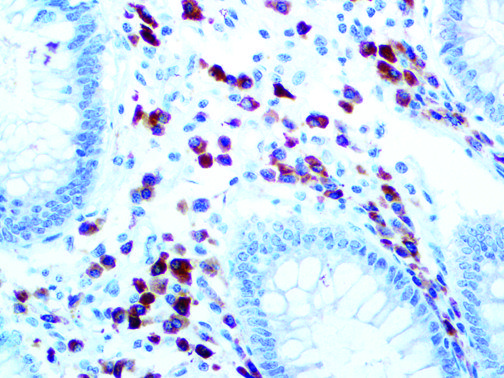

It is the ICU physician who is most likely to witness one of the deadliest manifestations of the abnormal immunological response, the cytokine storm syndrome (CSS). This response is also referred to by some as the cytokine release syndrome (CRS). CSS is characterized by continuous activation and expansion of macrophage and lymphocyte populations, which secrete large amounts of cytokines, causing the cytokine storm. This massive cytokine release is akin to hemophagocytic lymphohistiocytosis (HLH) disease, a syndrome characterized by initial unchecked and persistent activation of cytotoxic T lymphocytes and NK cells.

Clinical and laboratory manifestations of HLH include fever, enlarged liver and/or spleen, neurologic dysfunction, coagulopathy, liver dysfunction, cytopenias (i.e., low levels of erythrocytes, leukocytes, and/or platelets), hypertriglyceridemia, hyperferritinemia, hemophagocytosis, and eventually diminished NK cell activity as the immune system becomes progressively paralyzed. HLH can be familial (primary HLH) or secondary to another disease process (sHLH), such as rheumatic disease, in which it is referred to as macrophage activation syndrome (MAS, characterized by elevated ferritin).